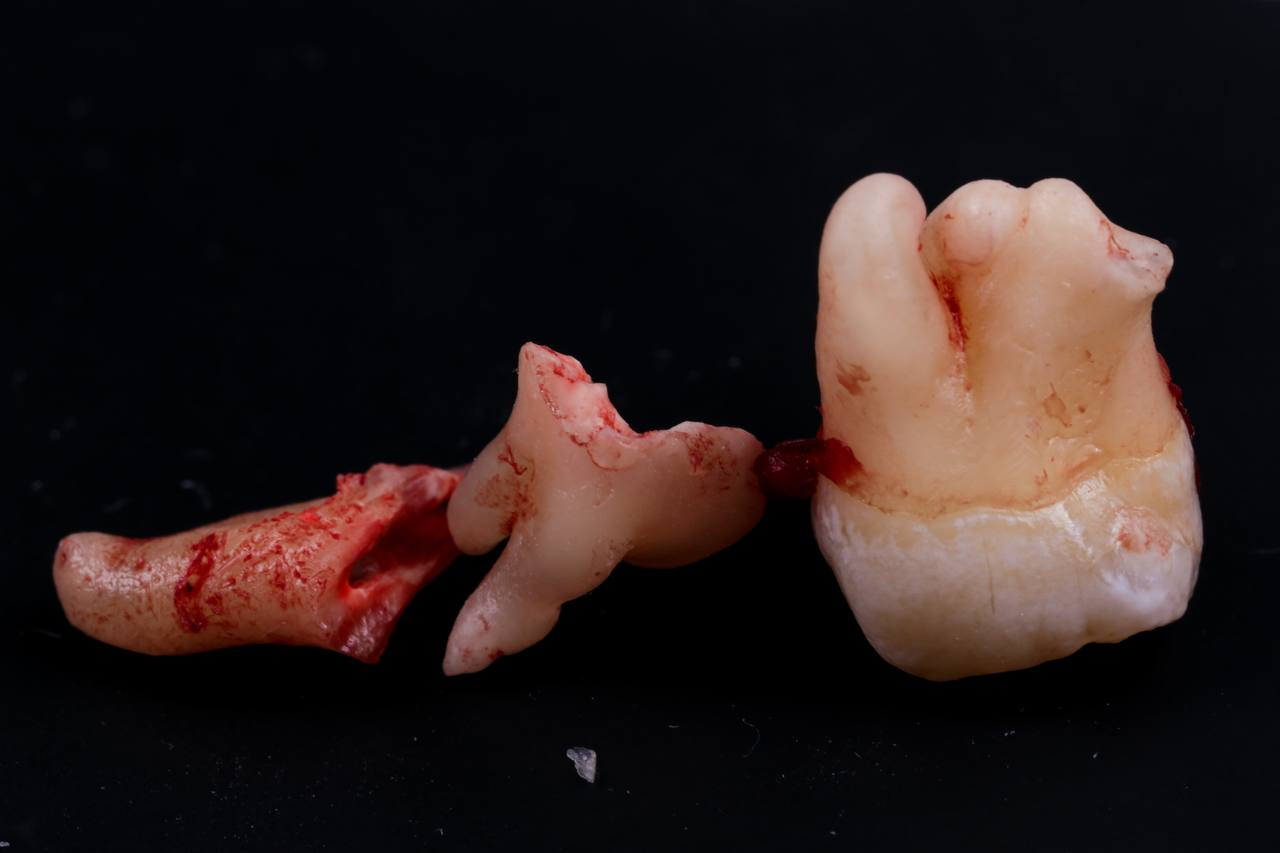

• Полное удаление зуба - если зуб полностью прорезался и имеет сросшиеся корни.

• Отдельное удаление коронки зуба и его корней - если зуб прорезан и корни растут по отдельности.

• Удаление зуба по схеме 1 или 2 с разрезом десен - если зуб прорезан частично.

• Разрез десен, освобождение зуба от близлежащей кости ультразвуком и удаление по схеме 1 или 2 - если зуб не прорезался, но беспокоит.